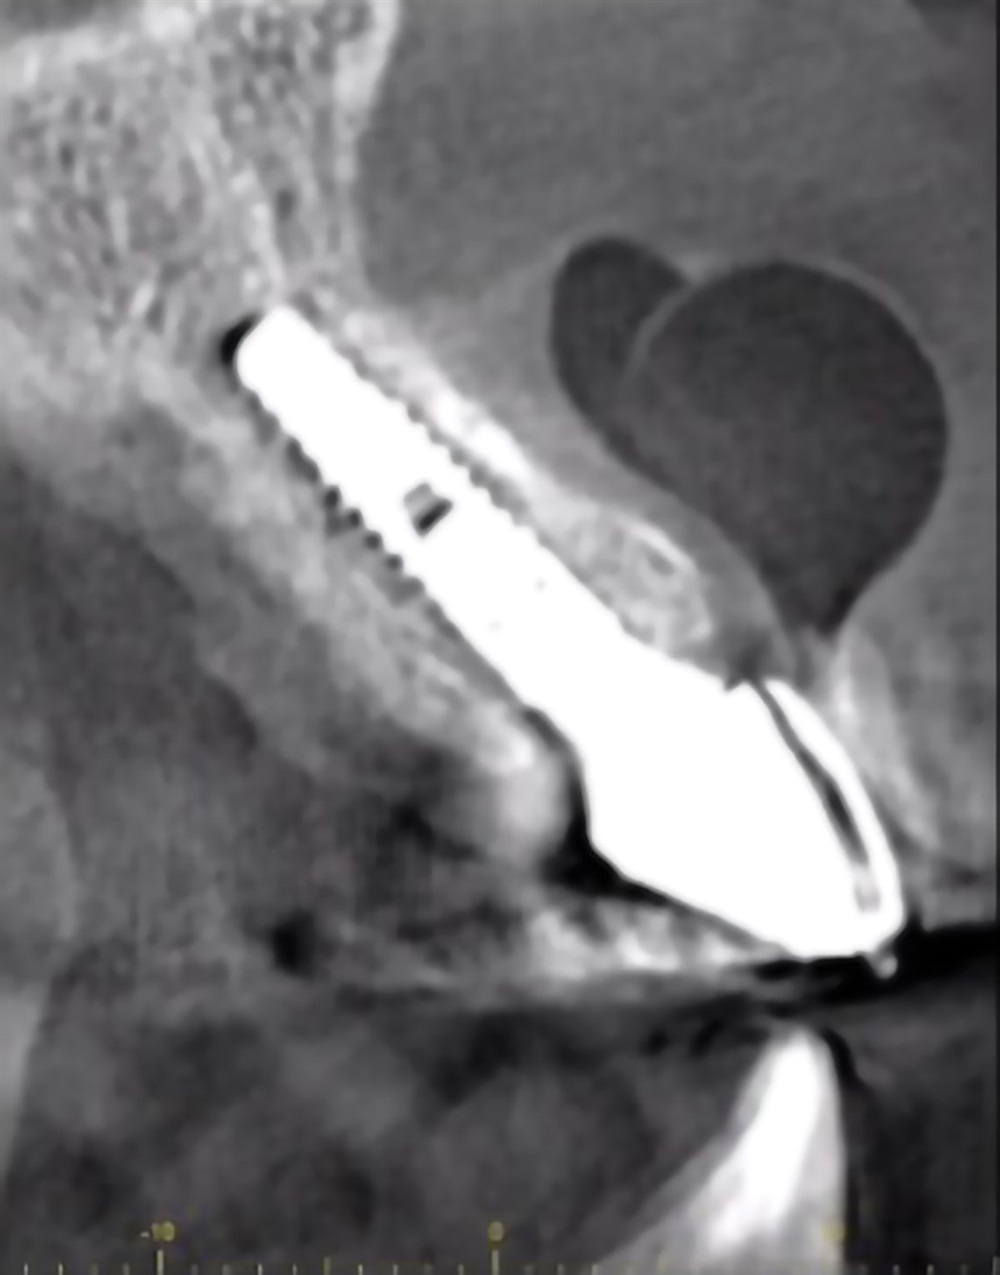

As part of my graduate program, I’m participating in a randomized controlled clinical trial that compares different membranes in extraction and preservation procedures. One of my faculty members is the principal investigator, and multiple residents work on different data sets. I’ll be studying hard tissues, measuring CT scans and bones before and after healing, to see if there is a difference in that hard-tissue volume maintenance between the two treatment modalities. (Essentially, trying to determine which membrane, if any, works better in preserving the bone for a future implant.)

Dentis implants. An implant with a tapered design, platform switching, and it’s available as both resorbable blast media (RBM) and sandblasted, large-grit, acid-etched (SLA) surface treatments. I find the surgical and prosthetic armamentarium very straightforward, and the built-in drill stops for each available length provide a strong safety margin. Also, both the healing and prosthetic abutments are designed with a concave emergence, which allows for thicker soft-tissue and subcrestal placement of the implants without impinging on the gingiva and bone.

This remains one of my favorite cases because it really displays the success one can have with anterior implant cases. I was using a modified “dual zone therapy” technique (developed by Drs. D.P. Tarnow and S.J. Chu), which I have found to have great utility in an office where making immediate provisionals does not fit the workflow.